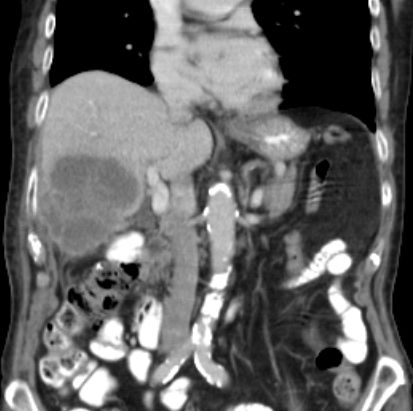

86-jähriger Mann, bei dem vor 9 Monaten eine Cholezystektomie wegen gedeckt perforierter Cholezystitis vorgenommen wurde. Jetzt Verdacht auf Leberabszess. Die laparoskopische Biopsie ergab ein Adenokarzinom. Die Nachbefundung der Gallenblase erbrachte immunhistochemisch den Nachweis eines Gallenblasenkarzinoms. | ||